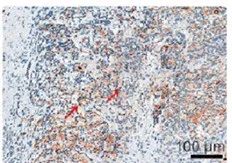

根据不同的实验需求,选择不同的染色方式,常见的染色方式有H&E、IHC、IF等。

对于有特殊实验需求的客户,还有多重荧光免疫组化试剂盒,能够满足多指标的染色需求。多重荧光免疫组化试剂盒提供从4色到7色的解决方案,爱必信也为有需要的客户提供多色的实验服务。

即用型高效免疫组化二抗试剂盒

货号:abs957